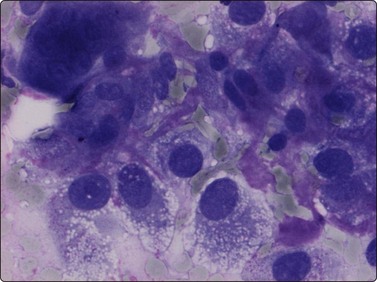

The cytological appearance of conventional ES is distinctive. Smears are generally highly cellular and are composed of both single cells and groups of loosely cohesive cells. The cells are fragile and naked nuclei as well as a faint gray–blue (MGG) background of detached cytoplasm are commonly seen. There is a characteristic mixture of two types of cells. One has abundant pale cytoplasm with vacuoles or large clear spaces, rounded or ovoid nuclei with finely granular chromatin and 1–3 small nucleoli (‘large light cells’). The other has scanty cytoplasm and irregular nuclei with dense chromatin (’small dark cells’). The two types of cells are most clearly distinguished within groups or clusters of cells, the small dark cells are interspersed, often as small molded groups, between large light cells (Fig. 16.31A). Rosette-like structures without a fibrillar center are occasionally present (Fig. 16.31B,C). The cytoplasmic vacuoles or clear spaces correspond to large deposits of glycogen (Fig. 16.31A).

image image image

Fig. 16.31 Ewing’s sarcoma

(A) A mixture of cells with larger pale-staining nuclei and cells with smaller and darker nuclei; note the cytoplasmic vacuoles and clear spaces in the pale cells (MGG, HP); (B,C) Rosette-like structure; nuclear chromatin and nucleoli more clearly seen in H&E than in MGG (A, H&E, HP; B, MGG, HP).